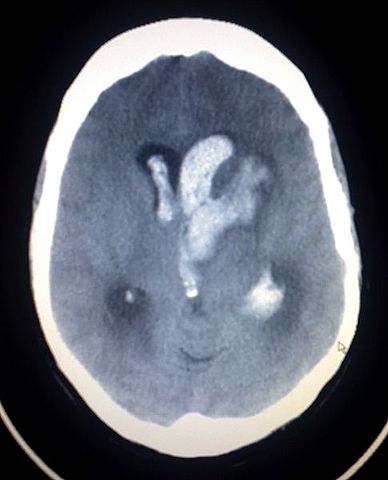

English: This image shows an Intracerebral and Intraventriclar haemorrhage of a young woman. The woman was one week post partum, with no known trauma involved.